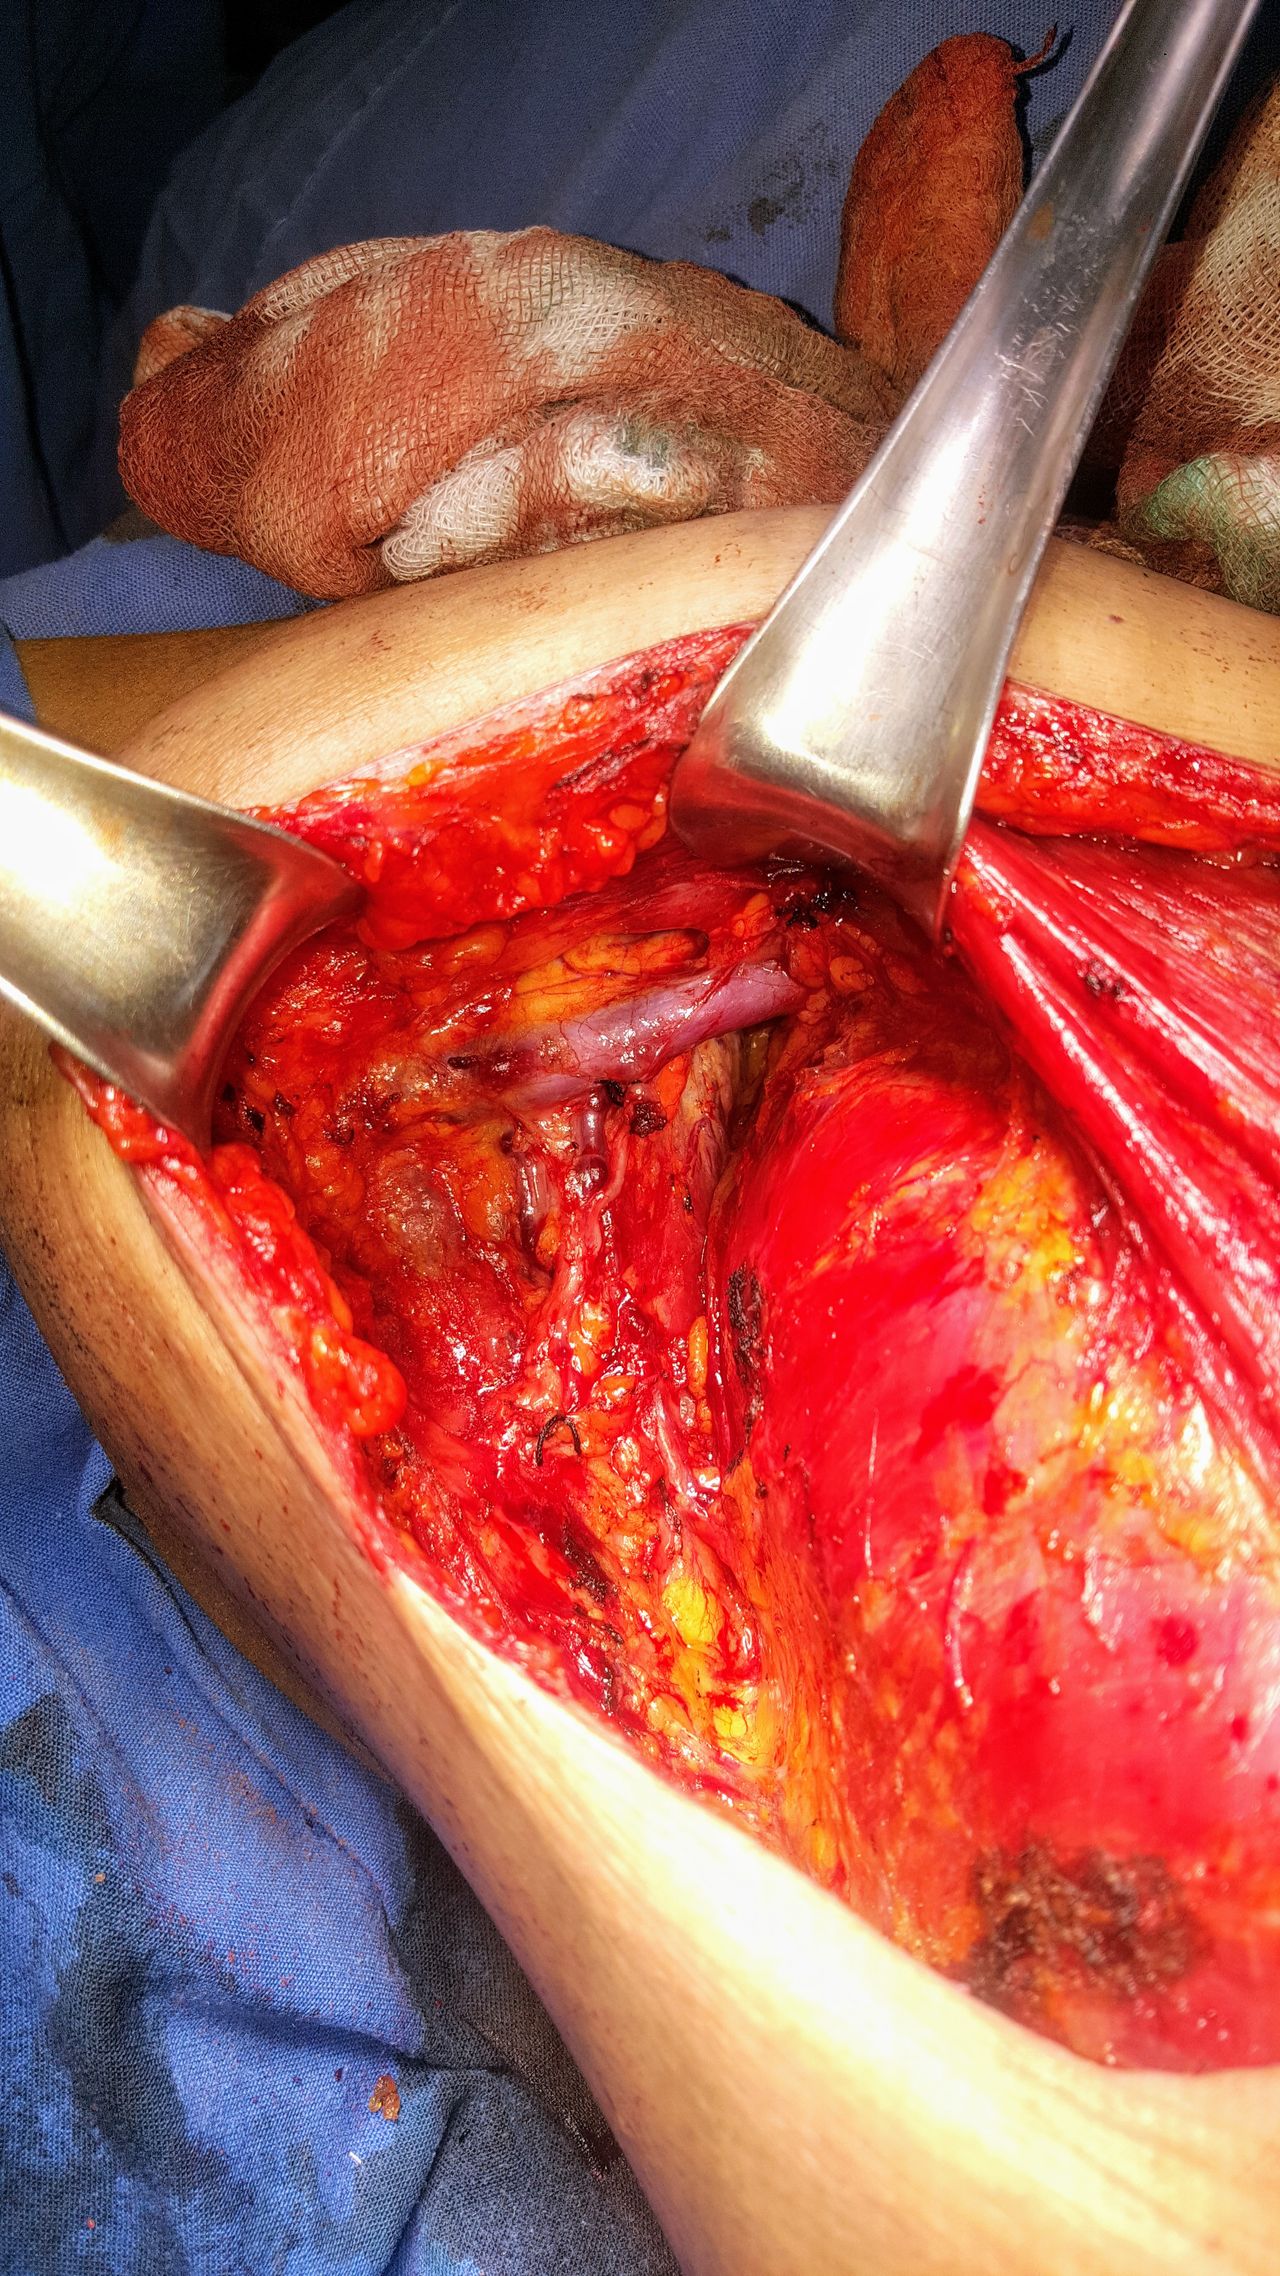

Cirugía ginecológica y obstetrica de alta complejidad

Cirugía vascular pélvica